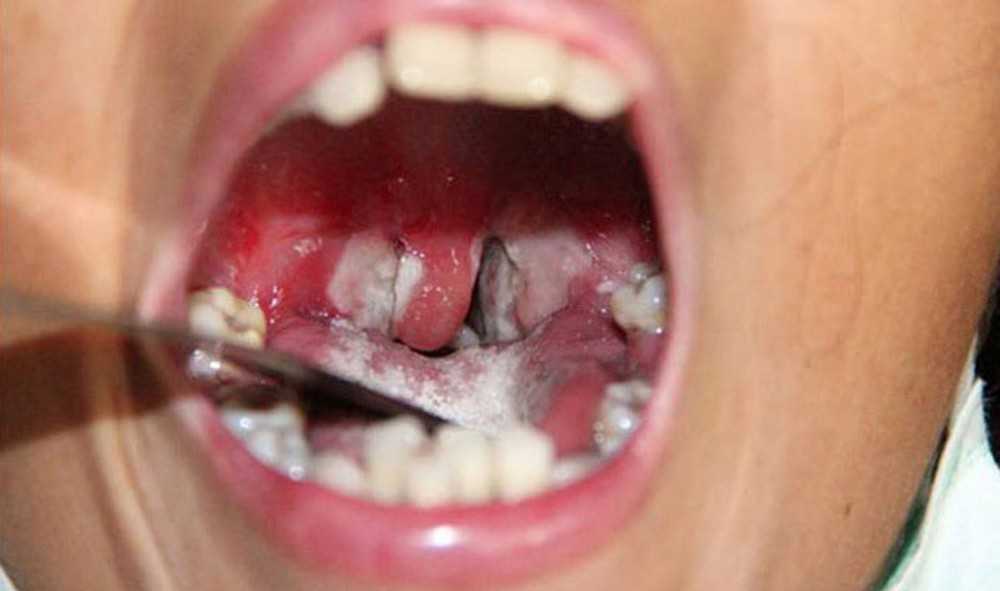

+ Sau 2-3 ngày, sẽ xuất hiện một đám hoại tử tạo thành lớp giả mạc màu trắng xanh, dai và dính chắc vào amiđan, hoặc có thể lan rộng bao phủ cả vùng hầu họng.

+ Khi khám, bác sĩ có thể thấy các giả mạc tại ngay thanh quản hoặc từ hầu họng lan xuống. Nếu không được xử trí kịp thời, các giả mạc này có thể gây tắc đường thở làm bệnh nhân suy hô hấp và có nguy cơ tử vong nhanh chóng.